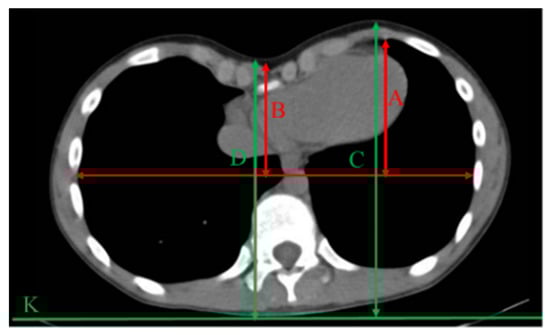

The CI3D is calculated by adapting the common correction index to the outer chest perimeter, as depicted in Figure 5.

Figure 5. The correction index 3D (CI3D).